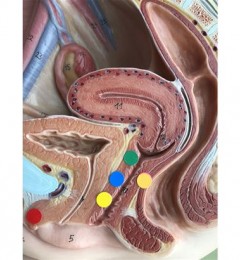

②三维一体,自然美观:在提取毛囊时,进行选择性提取,手术后提取区毛发与原状态无差异;单株分离后,在种植区选择性种植,并分层次多角度种植,利用1.0mm宝石刀+微针种植+PRP注射,达到脱发区域、供体部位、原有毛发三大区域三维一体,自然美观。

所谓的PRP,及自体血清,内含有多种生长因子和大量纤维蛋白,可快速修复创面作用,为修复细胞提供良好支架、收缩创面凝血作用,刺激软组织再生,促进伤口早期闭合防止感染。

③专利设备,3天恢复:采用新生专利设备(PAC)毛囊提取仪提取毛囊,提取环钻口径0.75mm,因为使用设备精细、可调控,创口很小,术后恢复只要3天。